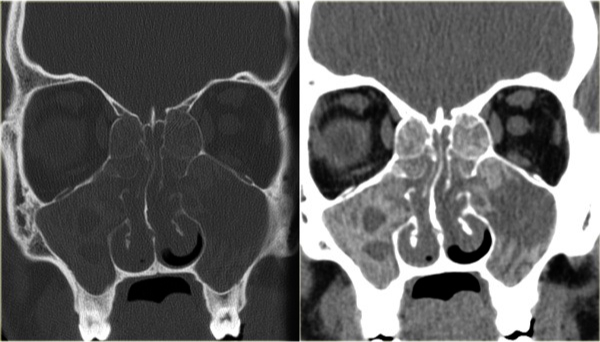

Chronic Rhinosinusitis

#ospe involved maxillary, ethmoid

Fungal sinusitis

heterogenous color, differences is fungal management is conservative; nasal spray, irrigation - no antifungals